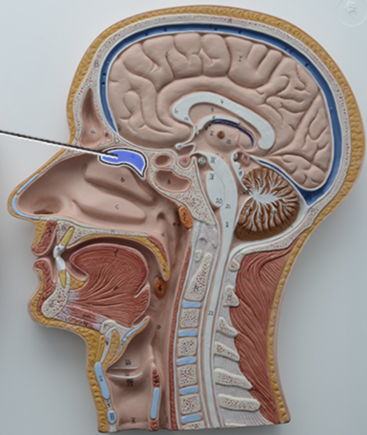

What structure is this?

Diaphragm

What structure is this?

Hard Palate

What structure is this?

Soft Palate

What structure is this?

Uvula

What structure is this?

Nasal cavity

What structure is this?

Superior Nasal Concha

What structure is this?

Middle Nasal Concha

What structure is this?

Inferior Nasal Concha

What structure is this?

The nasopharynx region of the pharynx

What structure is this?

The Oropharynx region of the pharynx

What structure is this?

The Laryngopharynx region of the pharynx

Nasal Septum